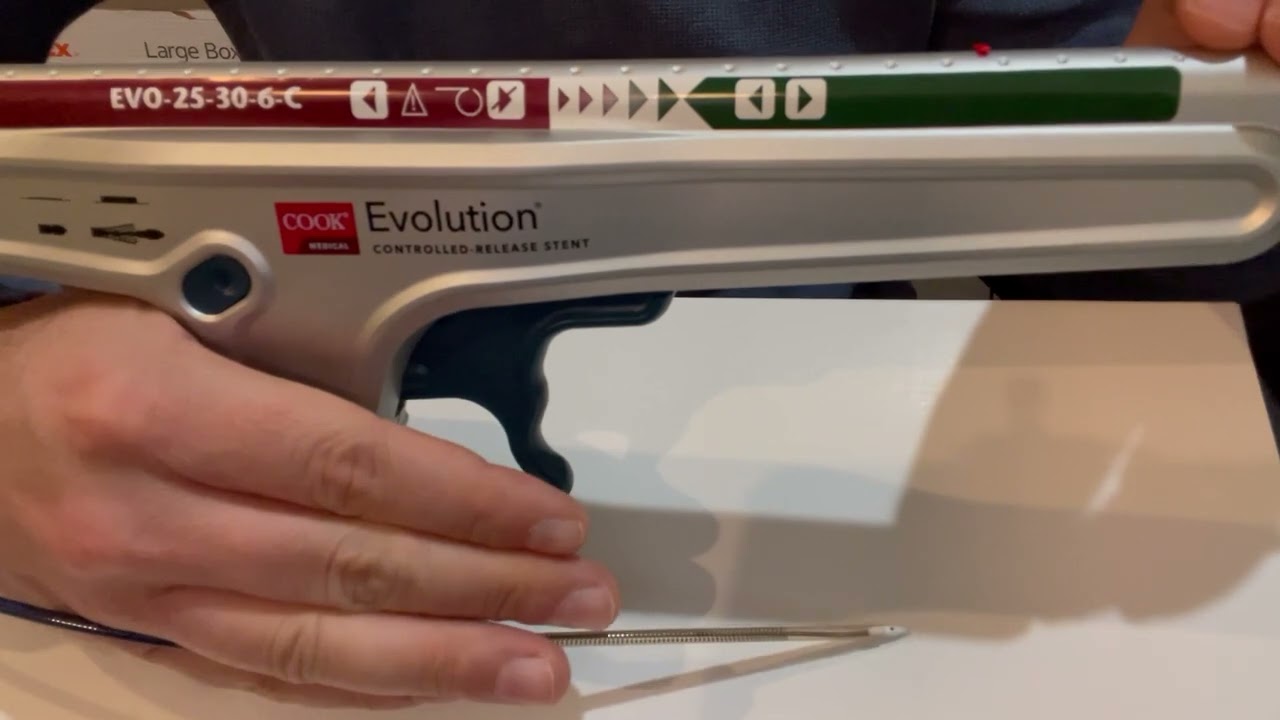

Dr. Hady Lichaa describes the management of a migrated iliac artery stent, with snaring into an adequate position.